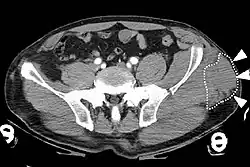

Image is of a computed tomography (CT) image of a Morel-Lavallee lesion.

Computed tomography (CT) image of the pelvis depicting a closed internal degloving injury (Morel-Lavallée lesion). CT is shown in the axial plane. The white dotted lines and white arrows indicate a collection of blood inside the lesion. A fracture of the left iliac wing is also visible on the CT.[10]